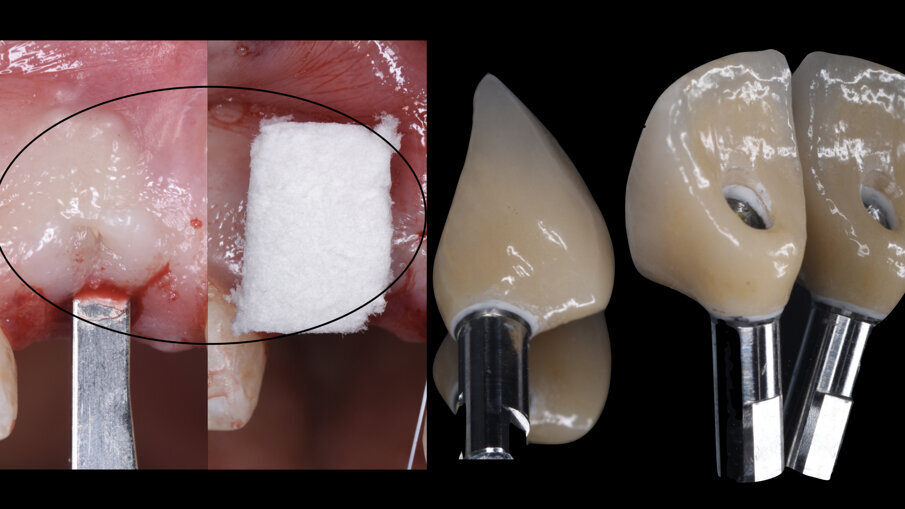

È stata quindi eseguita un’incisione vestibolare intrasulculare del sito senza toccare le papille, facendo scorrere la lama sul piano osseo crestale, e nella porzione più apicale dove era presente la discontinuità della corticale si è spostato la lama mesiale e distale e ancora apicale fino a ritrovare il piano osseo secondo le indicazioni della CBCT; è stato possibile così inserire una membrana in collagene suina Geistlich Bio-Gide (Geistlich Pharma AG, Wolhusen, Switzerland) opportunamente sagomata in modo che avesse un appoggio sui piani ossei (Fig. 4); all’interno dell’alveolo è stato posizionato Geistlich Bio-Oss Collagen (Geistlich Pharma AG, Wolhusen, Switzerland), osso bovino deproteinizzato con un 10% di collagene suino addizionale, materiale osteoconduttivo che oltre a essere mantenitore di spazio e scaffold per la rigenerazione ossea, funge anche da sostegno per il tessuto molle soprastante (Fig. 5). Si è quindi proceduto dopo anestesia palatale a un prelievo tramite bisturi circolare di un punch epitelio connettivale di forma tondeggiante e misure simili all’alveolo dell’1.1 da sigillare; dopo la disepitelizzazione dei margini dell’alveolo si è proceduto alla sutura del punch al di sopra del sostituto osseo con suture Vicril 6-0 (Johnson & Johnson Medical Spa, Pomezia RM, Italia) con punti staccati alle quattro estremità e sutura a materassaio esterno incrociato compressiva (Fig. 6). In questa fase la paziente è stata riabilitata con un maryland bridge in composito cementato adesivamente.

A livello dell’impianto 1.1 è stata inserita a busta una matrice eterologa volumetricamente stabile di origine suina Geistlich Fibro-Gide (Geistlich Pharma AG, Wolhusen, Switzerland) (Fig. 12) stabilizzata con una sutura riassorbibile Vicril 6-0 (Johnson & Johnson Medical Spa, Pomezia RM, Italia) che grazie alla sua ottima integrazione e stabilità nel tempo7 permetterà di ricostruire la bozza radicolare e ottenere un ideale volume dei tessuti molli attorno all’impianto.